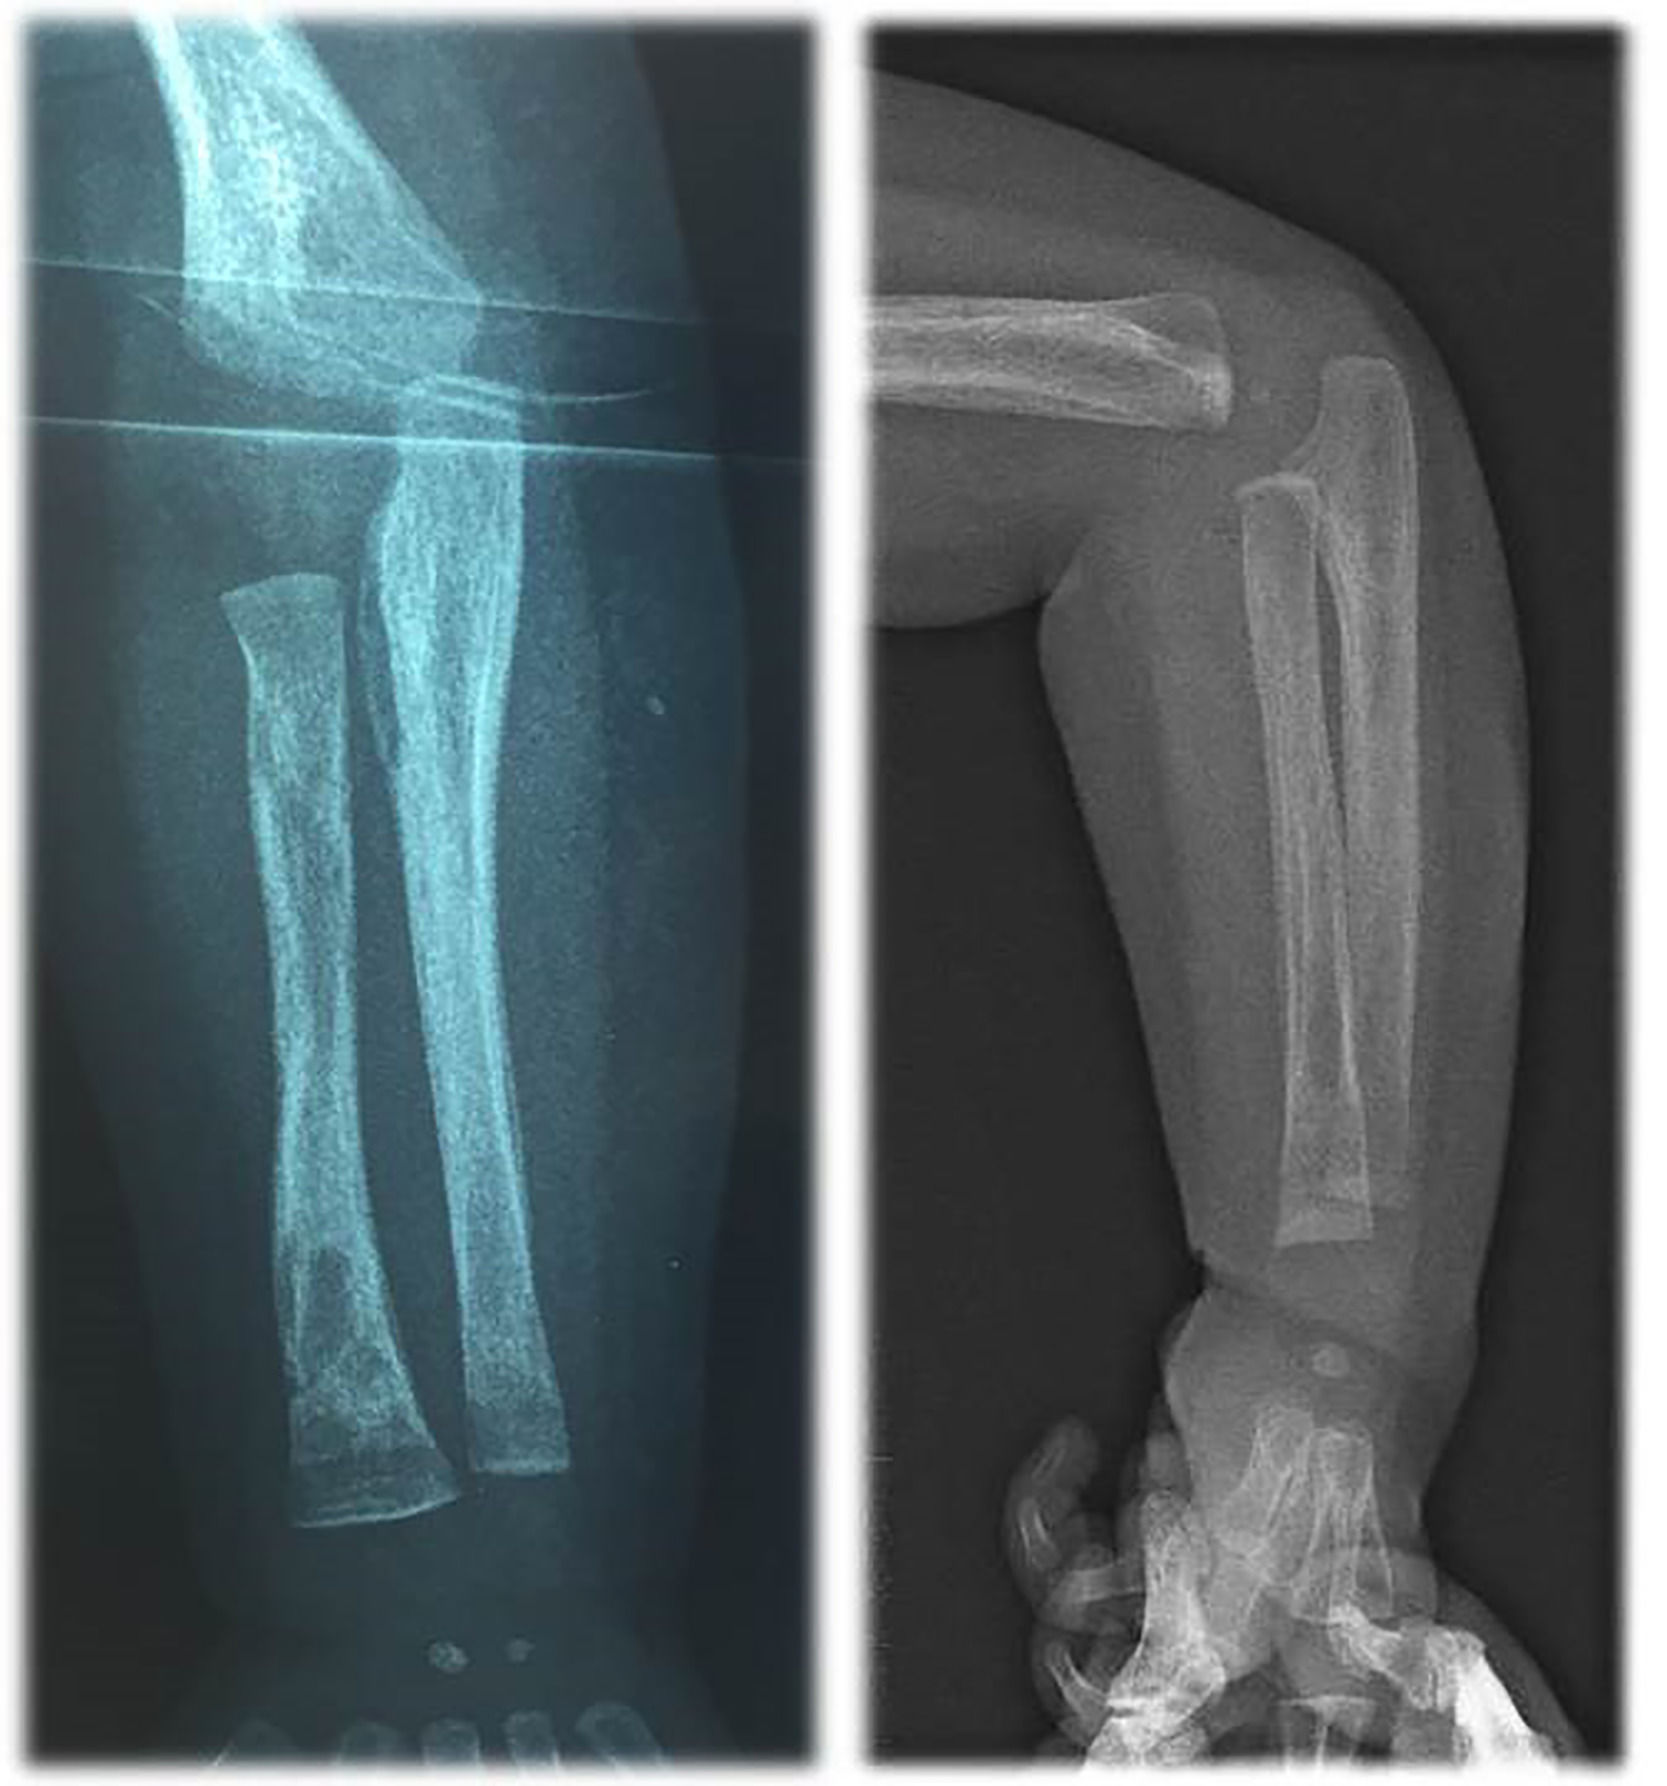

Blood tests showed: aregenerative normocytic anaemia (7.7 g/dL of hemoglobin), elevated C-reactive protein (160 mg/L), elevated white blood cells (28 G/L) with a high lymphocytosis (13 G/L). Liver tests showed mild cytolysis without cholestasis. Chest X-Ray was normal. Urine cytology and culture, lumbar fluid tests and culture, repeated blood cultures, and viral serologies were negative. Empirical antibiotic treatment with amoxicillin/clavulanate was initiated, then replaced by cefotaxime for six days without improvement. Because of the persistence of fever despite antibiotic treatment, other infectious causes were investigated: a 99mTc-diphosphonates scintigraphy showed a left wrist hyperfixation, and the further wrist X-Ray diagnosed a periostitis and osteomyelitis of the radius (Fig. 1), but the lesions were too small for biopsy. The antibiotics were then replaced by cefazolin and clindamycin for six days. MRI of the left wrist did not confirm osteomyelitis; so, antibiotics were discontinued. Echocardiography showed an intracardiac mass (15 × 8 mm) on the posterior wall of the right atrium extending to the origin of the superior vena cava. Cardiac MRI showed an intracardiac mass attached to the posterior wall and interatrial septum with a T2 hypo-signal, without enhancement after gadolinium injection (Fig. 2). Three hypotheses were considered: a right atrial myxoma (unlikely, however, due to non-enhancement after gadolinium injection), thrombosis of the superior vena cava, or a large Chiari network, which is a fenestrated, net-like embryonic remnant of the sinus venosus valves. One month later, in view of the finding of multifocal involvement, and persistent fever with persistent lymphocytosis elevation of liver enzymes, toxoplasmosis and syphilitic serology were performed. The Treponemal Hemagglutination Assay (TPHA) was superior to 10,240 and the VDRL (non-treponemal agglutination assay) was equal to 1:32. A new test on the mother revealed positive VDRL (1:8) and TPHA (> 10,240) tests. This child was born into a family with a low economic and social status, and the mother later reported several sexual partners. The infant was treated for 10-days with penicillin-G, administered at a dose of 250,000 units/kg/day, as recommended.4 Fever subsided on the first day, but a study of lymphocyte count and CRP showed that the inflammation had not been resolved. Thirteen days after the end of antibiotics, a second antibiotic course was prescribed: penicillin-G, administered at a dose of 150,000 units/kg/day for 15-days. Then a third cure was prescribed 10-days after the end of the second one, with the same posology. The effect of this prolonged antibiotic therapy led to a negative CRP and good infant health. However, the right atrial mass did not decrease and hyperlymphocytosis persisted. The infant was discharged after 4-months in hospital.

Cardiac-MRI comparison of intracardial mass (arrow) between the diagnosis and (a‒b) 20-months follow-up (c). T2 TrueFISP Sequence: Right intra-auricular mass at T2, attached to the posterior surface of the atrium and to the posterior part of the inter-atrial septum. Sequence after gadolinium injection: No lesion enhancement. Complete regression of intra-atrial mass.

Follow-up at 24-months showed a good clinical evolution, with slow disappearance of the cardiac mass, with negativation of VDRL. TPHA rates remained positive and stable over the course of the evolution. The boy showed good psychomotor development and growth. No other signs of syphilis were found. The intracardiac mass disappeared at the 20-month follow-up echocardiography (Fig. 3Figure 3).